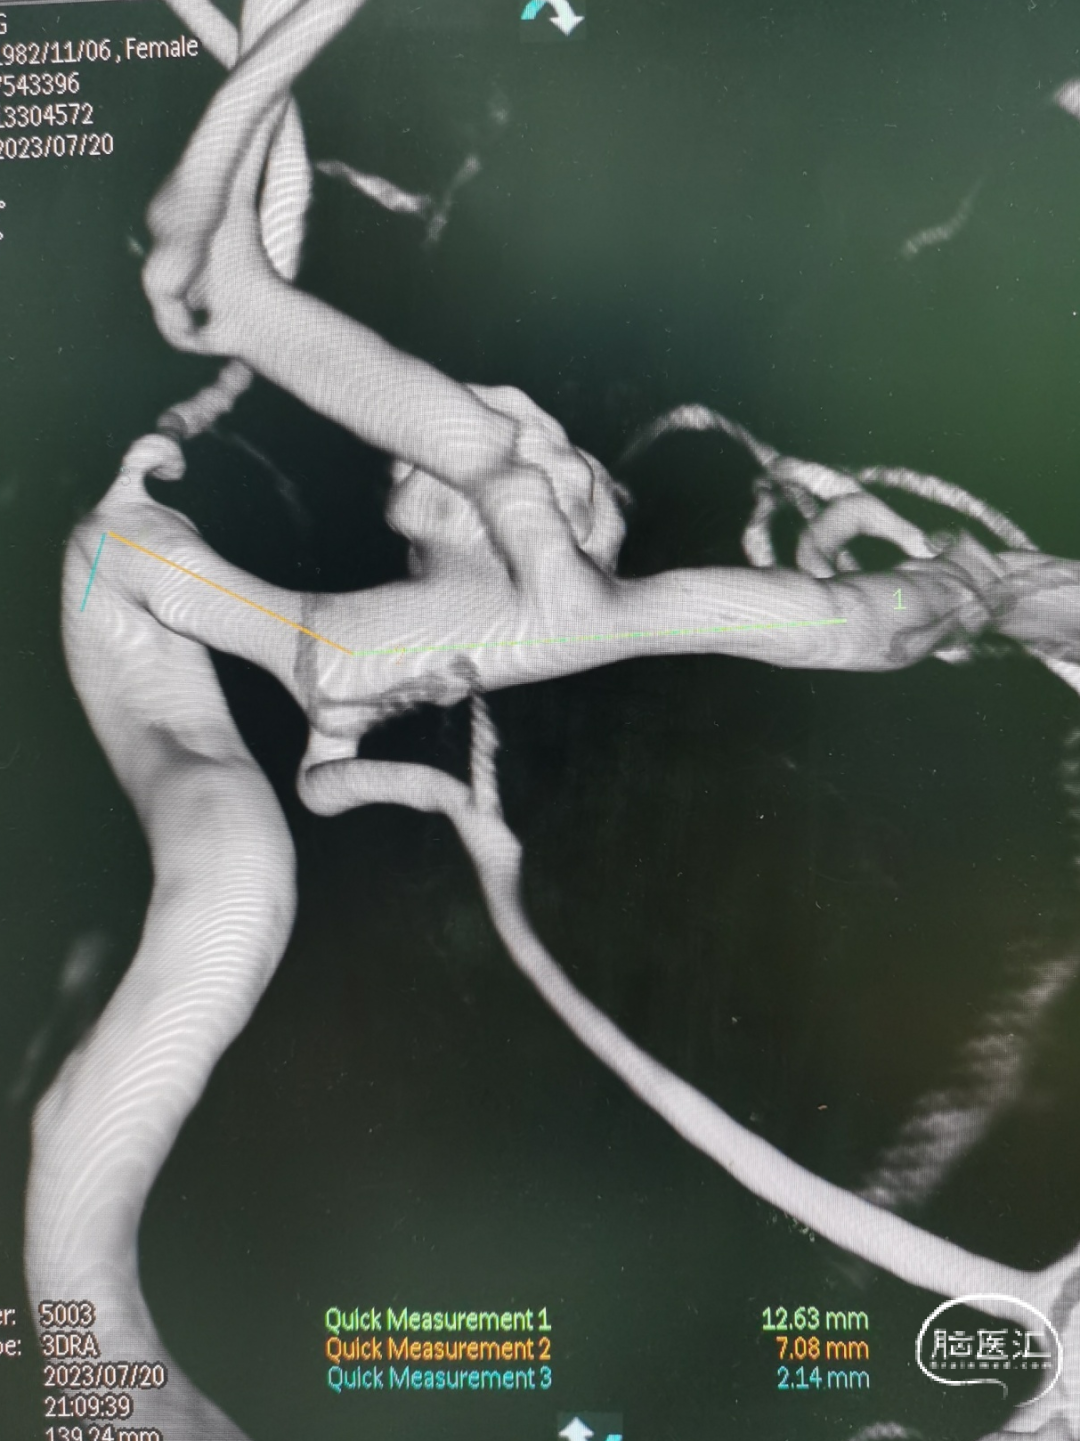

复查3D造影显示:3.5mm*4.4mm*3.2mm颈内末端动脉瘤一期采用Atlas支架辅助弹簧圈栓塞术后2周复发,动脉瘤体增大。

3D重建测量:

1)动脉瘤大小6.2*4.7mm

2)FD覆盖长23mm

3)远端血管2.4mm,近端血管3.5mm

动脉瘤的大小在短期内体积迅速增大,证实为血泡样动脉瘤。